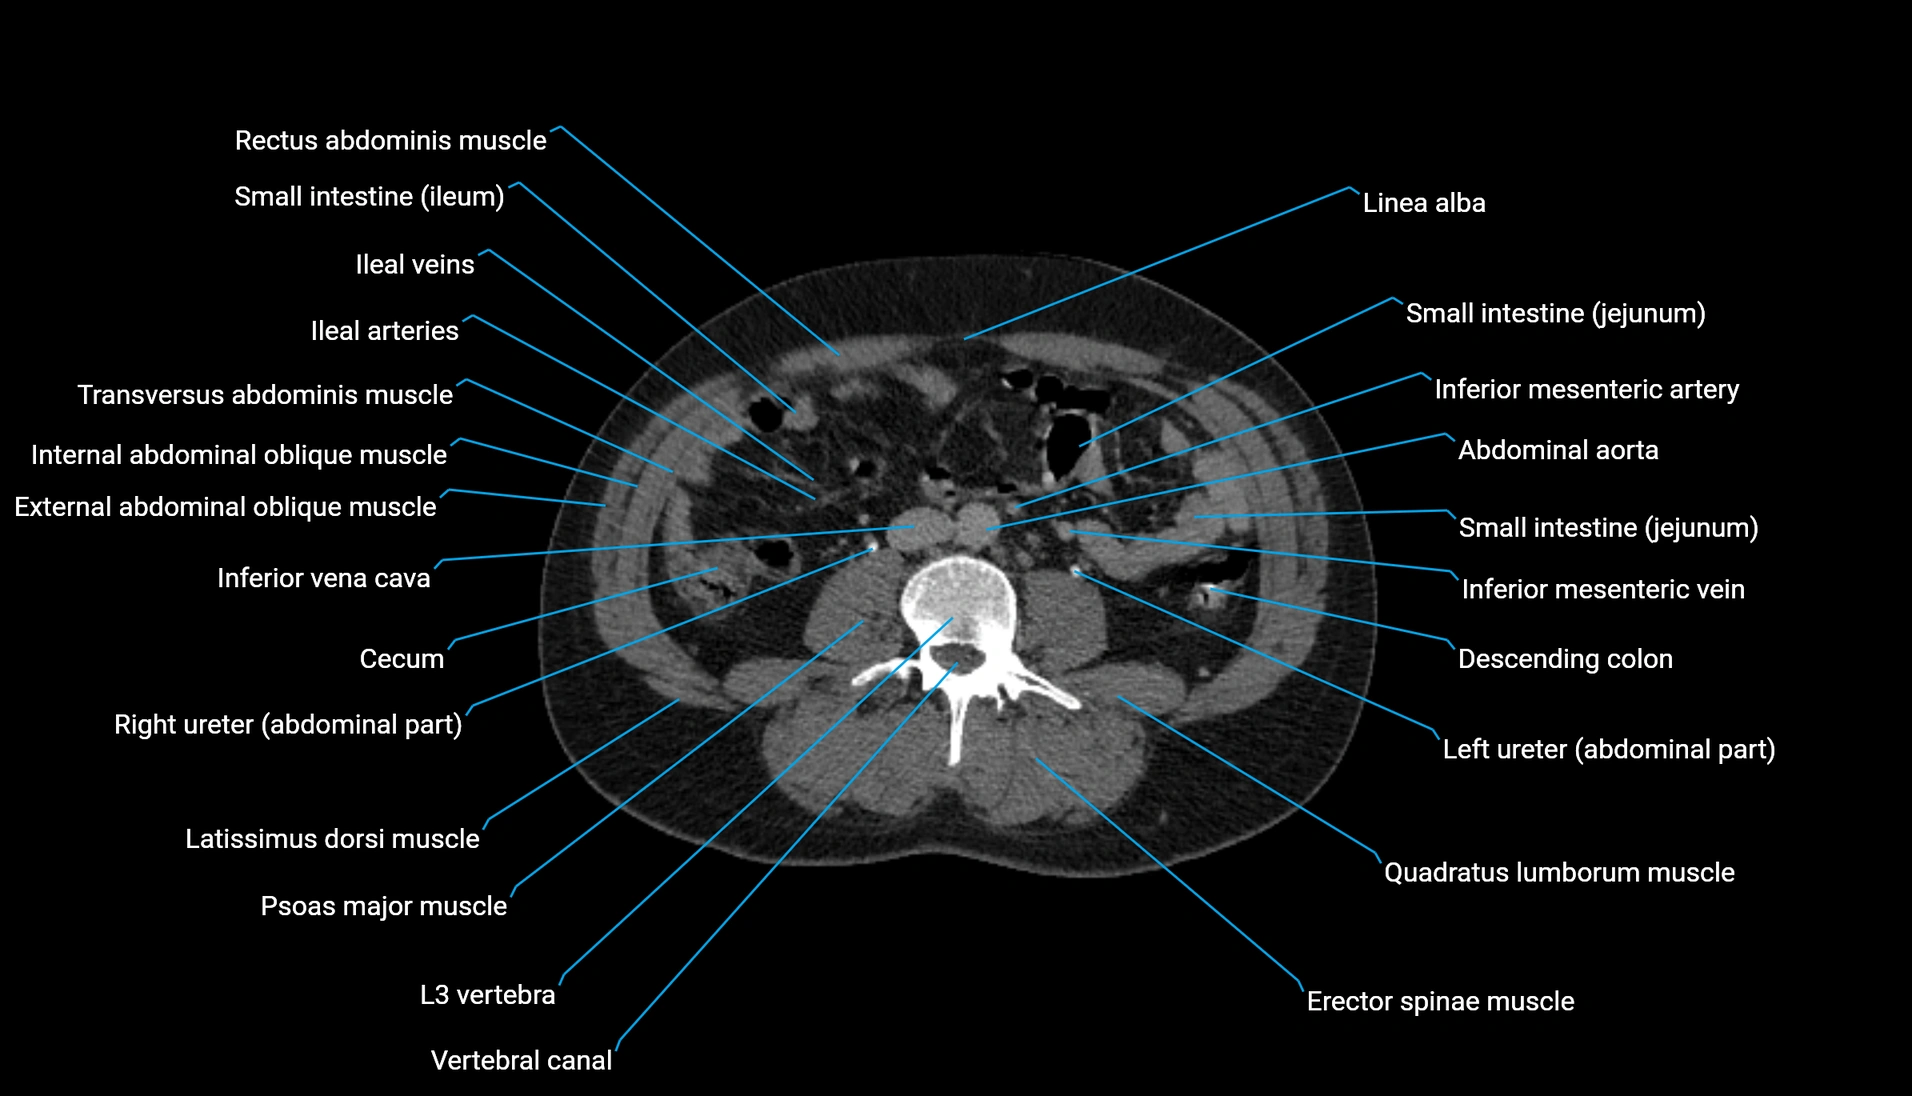

CT Appearance

Non-contrast CT:

-

Demonstrates cortical bone of acetabular rim in excellent detail

Detects fractures, dysplasia, retroversion, or bony overcoverage (pincer impingement)

3D reconstructions used in preoperative hip surgery planning

CT VRT 3D image

CT image